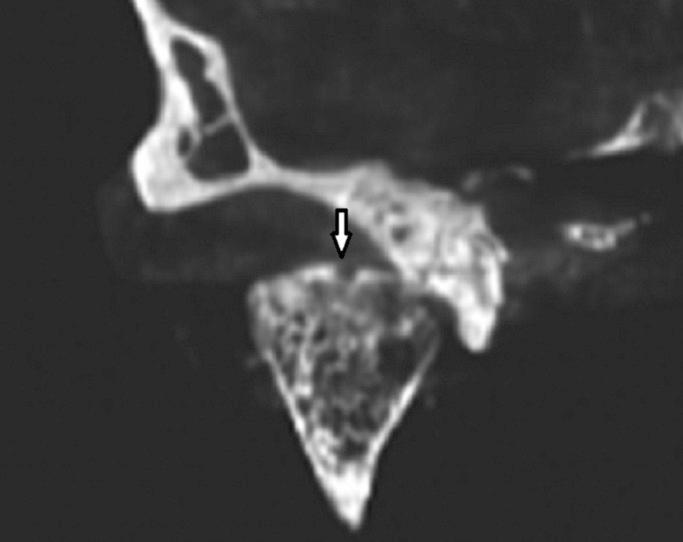

Radiographic examination is one of the most important parts of the clinical assessment routine for temporomandibular disorders. The aim of this study was to compare the diagnostic accuracy of cone-beam computed tomography(CBCT) with panoramic radiography and spiral computed tomography for the detection of the simulated mandibular condyle bone lesions.

The sample consisted of 10 TMJs from 5 dried human skulls. Simulated erosive and osteophytic lesions were created in 3 different sizes using round diamond bur and bone chips, respectively. Panoramic radiography, spiral tomography and cone-beam computed tomography were used in defect detection. Data were statistically analyzed with the Mann-Whitney test. The reliability and degrees of agreement between two observers were also determined by the mean of Cohen's Kappa analysis.

CBCT had a statistically significant superiority than other studied techniques in detection of both erosive and osteophytic lesions with different sizes. There were significant differences between tomography and panoramic in correct detection of both erosive and osteophytic lesions with 1mm and 1.5 mm in size. However, there were no significant differences between Tomography and Panoramic in correct detection of both erosive and osteophytic lesions with 0.5 mm in size.

CBCT images provide a greater diagnostic accuracy than spiral tomography and panoramic radiography in the detection of condylar bone erosions and osteophytes. Key words:Bone defect, Condyle, CBCT, Panoramic, radiography.

影像学检查是颞下颌关节紊乱病临床评估常规中最重要的部分之一。本研究的目的是比较锥形束计算机断层扫描(CBCT)与全景放射摄影和螺旋计算机断层扫描在检测模拟下颌髁突骨病变方面的诊断准确性。

样本包括来自5个干燥人类头骨的10个颞下颌关节。分别使用圆形金刚石钻和骨屑制作了3种不同大小的模拟侵蚀性和骨赘性病变。在缺陷检测中使用了全景放射摄影、螺旋断层扫描和锥形束计算机断层扫描。数据采用曼-惠特尼检验进行统计分析。两位观察者之间的可靠性和一致性程度也通过科恩卡方分析的平均值来确定。

在检测不同大小的侵蚀性和骨赘性病变方面,CBCT在统计学上比其他研究技术具有显著优势。在正确检测大小为1mm和1.5mm的侵蚀性和骨赘性病变方面,断层扫描和全景放射摄影之间存在显著差异。然而,在正确检测大小为0.5mm的侵蚀性和骨赘性病变方面,断层扫描和全景放射摄影之间没有显著差异。

在检测髁突骨侵蚀和骨赘方面,CBCT图像比螺旋断层扫描和全景放射摄影具有更高的诊断准确性。关键词:骨缺损;髁突;CBCT;全景;放射摄影。